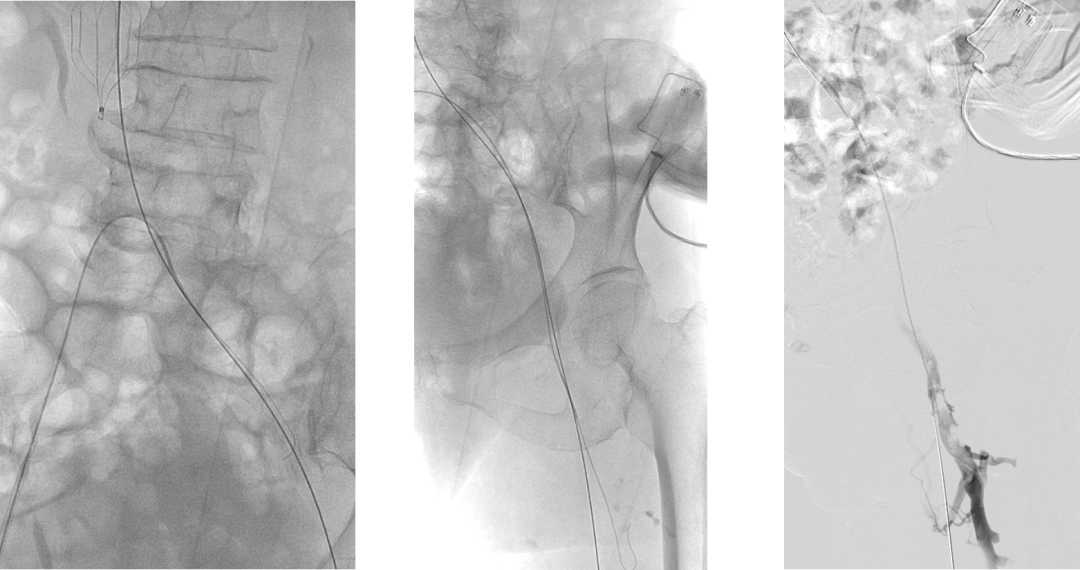

左腘静脉穿刺置鞘,对近端血栓行AngioJet喷注尿激酶后吸栓,吸栓后股浅静脉恢复通畅

复查造影:股深静脉内血栓,股总静脉血流瘀滞,左髂静脉狭窄行PTA

Simon导管翻山后导丝进入股深静脉,造影明确股深静脉血栓范围

股深静脉吸栓后通畅,于左髂静脉置入14*80mm支架,复查造影血流均通畅